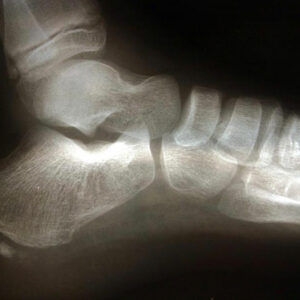

4 effective treatments for heel spur relief

A heel spur is a bone growth that develops on the heel bone, specifically on the underside of the bone. It happens due to calcium deposit that causes a bony protrusion of nearly half-inch to develop on the heel bone. The calcium deposition occurs gradually over months. An extreme, persistent strain on the ligaments and foot muscles, repeated instances of heel bone membrane tearing, and plantar fascia stretching are some of the common causes of heel spur.

3 natural treatments for heel spur relief

Commonly affecting athletes who frequent activities include running and jumping, heel spur is caused due to calcium deposits on the underside of the heel bone. The symptoms include inflammation of tissues and tendons near the spur, pain while walking or jogging, formation of calluses, swelling or redness of the affected part of the heel.